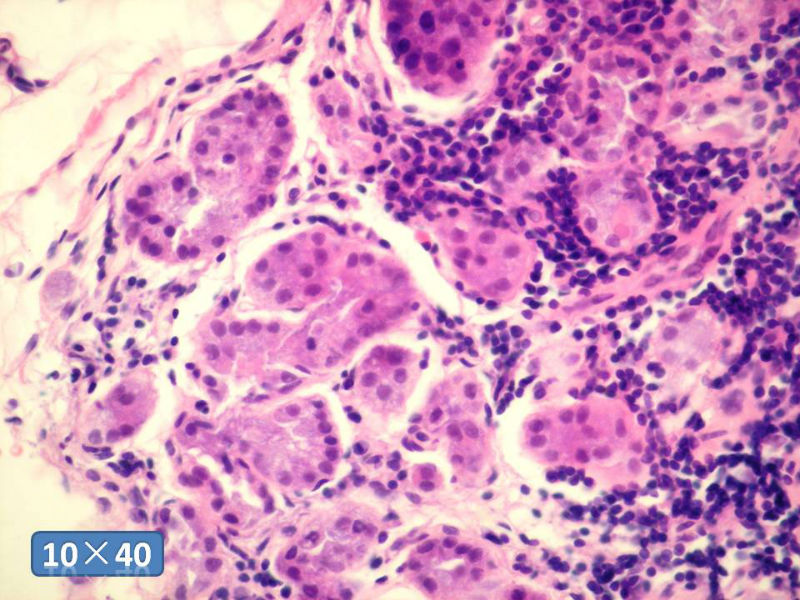

女性,50岁,乳腺肿物,冰冻切片(图1-25)

HE

IDC